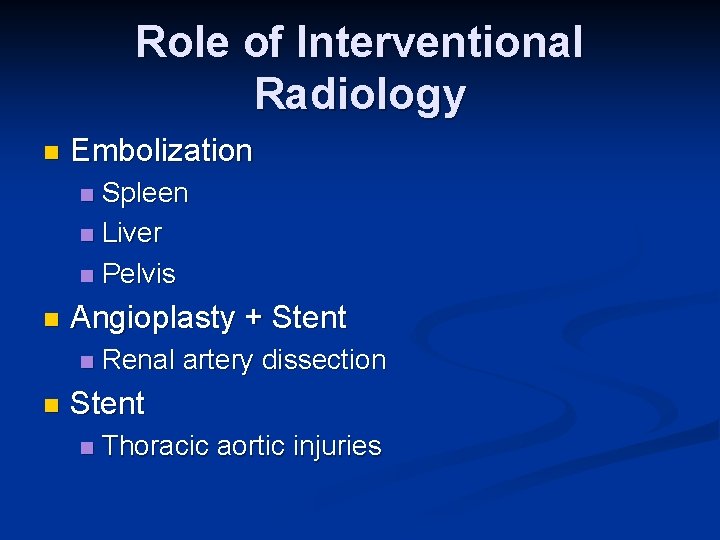

Role of Interventional Radiology n Embolization Spleen n Liver n Pelvis n n Angioplasty + Stent n n Renal artery dissection Stent n Thoracic aortic injuries